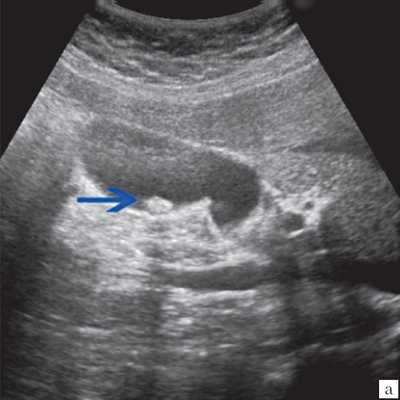

Материалы и методы. Исследование и лечение проводилось на базе детского хирургического стационара МУЗ ГКБ № 20 им. И.С. Берзона г. Красноярска, в котором проходили лечение 25 детей в возрасте от 1 мес. до 14 лет с врожденными кистами желчных протоков. При обследовании детей использовали клинико-лабораторную диагностику и инструментальные методы исследования: УЗИ в 100%, КТ - 50%, интраоперационная холецистография - 40%, ЭРХПГ -20%, лапароскопия - 20%. Эхографически киста общего желчного протока определялось как округлое или овальное анэхогенное образование, локализующееся в области головки поджелудочной железы и не связанное с желчным пузырем. Компьютерная томография полностью подтвердила данные, полученные при сонографическом исследовании. Следует отметить, что использование эндоскопической ретроградной холангиопанкреатографии позволяет выявить наиболее точную картину поражения общего желчного хода при сохранности проходимости в дистальной его части. На основании полученных данных решался вопрос о выборе метода хирургического лечения. Таким образом, дооперационная диагностика кистозной трансформации желчевыводящих путей в настоящее время значительно улучшилась благодаря применению современных методов исследования. Однако, выбор оперативного метода лечения окончательно может быть произведен только во время операции, так как решающее значение в верификации диагноза имеют интраоперационные рентгеноконтрастные методы исследования, которые позволяют выявить кистозные расширения вне- и внутрипеченочных желчных протоков, степень и протяженность их дилятации, проходимость терминального отдела холедоха, рубцовые сужения печеночных протоков, билиопанкреатический рефлюкс. В настоящее время предложен новый метод распознавания и лечения врожденной патологии желчевыводящей системы, включающий в себя комбинированное применение лапароскопии, чрезкожной чрезпеченочной холецистохолангиографии в сочетании с рентгенологическим контролем (под контролем электронно-оптического преобразователя) в режиме реального времени. К положительным сторонам данного метода относится: а) возможность применения у новорожденных детей; б) естественное (антеградное) введение контрастного вещества не допускает развития восходящего холангита; в) минимальная травматичность, г) высокая информативность, д) возможность в некоторых случаях устранять препятствие в области желчного протока.

Ультразвуковое исследование выполнено всем больным детям в 100%, что позволило в 60% поставить диагноз киста холедоха, КТ 7 детям (38%) с целью дифференциальной диагностики и уточнения топического расположения кисты, интраоперационная холецистография в 4 случаях (22 %), ЭРХПГ 3 пациентам (20%), лапароскопия 3 пациентам (20%).